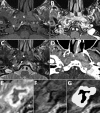

Description:We report a case of malignant otitis externa with jugular vein thrombosis caused by Aspergillus flavus. Magnetic resonance imaging revealed an unusual ink smudge pattern deep in a cervical abscess. The pattern was consistent with mycetoma and may be important for diagnosing these life-threatening infections.